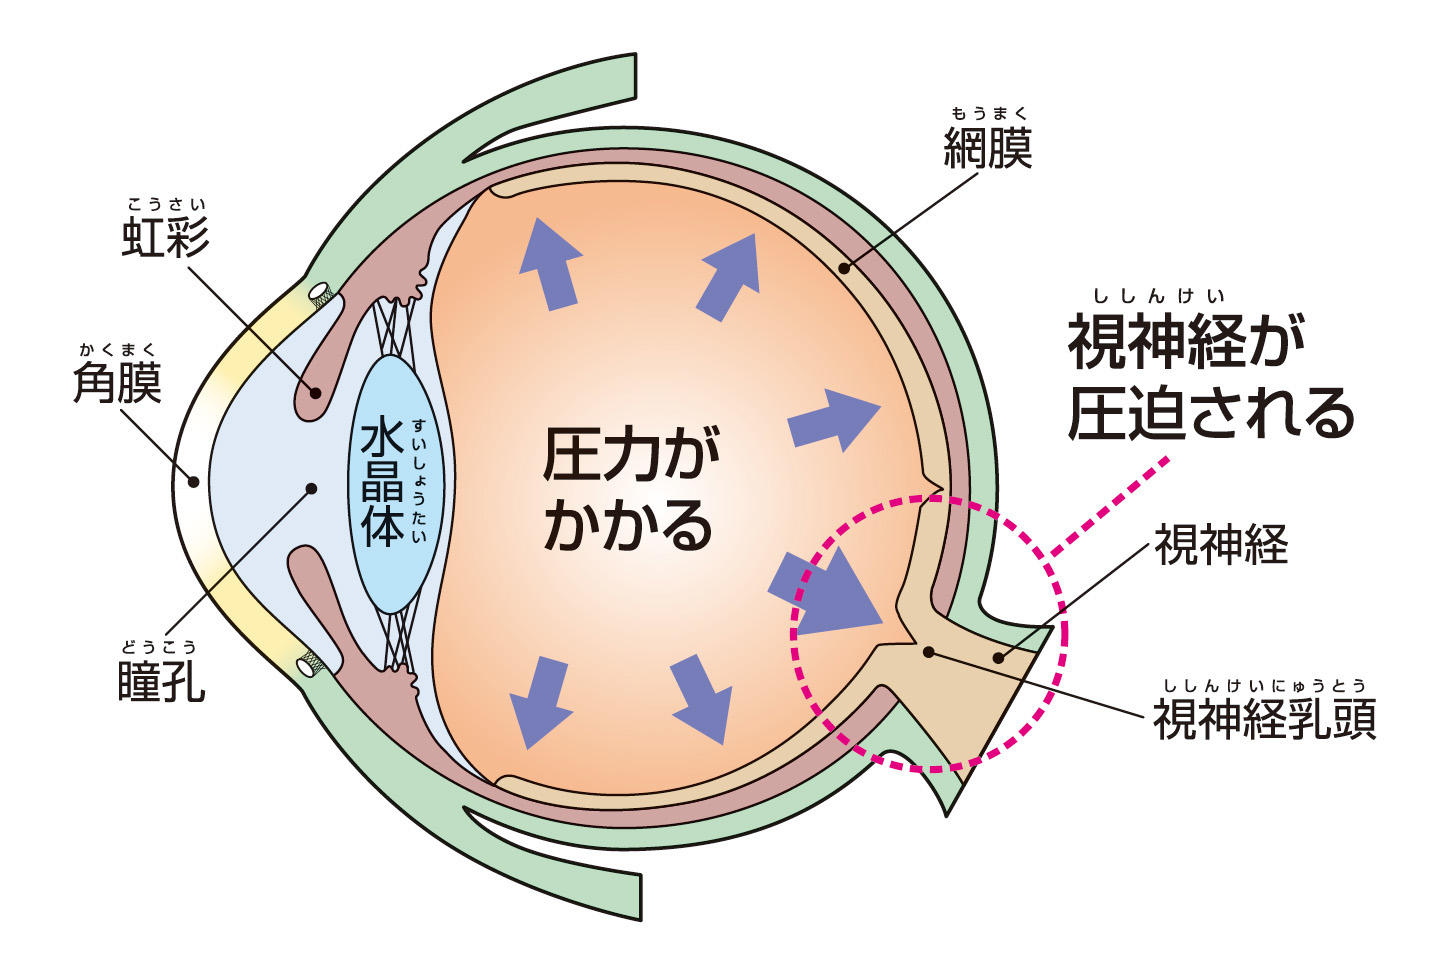

閉塞隅角緑内障は、眼の中の圧力が高くなりすぎる病気です。

治療せずに放置すると、あらゆる種類の緑内障が視神経(脳に視覚情報を伝える神経)に損傷を与え、最終的には失明に至る可能性があります。

閉塞隅角緑内障の場合、眼から液体が正常に流れ出ないため、圧力が高まります。

液体は、虹彩の後ろの眼の後房で生成されます。この液体は通常、瞳孔を通って眼球の前房に流れ込みます。

次に、液体は小柱網と呼ばれる一連のチャネルを通って、強膜 (白目) の静脈に流れ込みます。

閉塞隅角緑内障では、小柱網が閉塞または損傷します。液体はこの排水経路を容易に通過できないか、完全にブロックされています。この液体のバックアップにより、眼球内の圧力が上昇します。